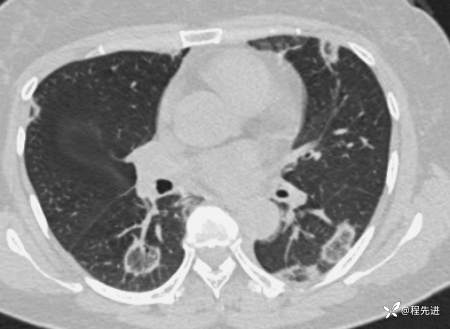

【心胸】特别精彩病例|胸闷1月余,好漂亮的反晕征呀

患者性别:女

患者年龄:57岁

简要病史:胸闷1月余

抗中性粒细胞胞质抗体相关性血管炎 (15)